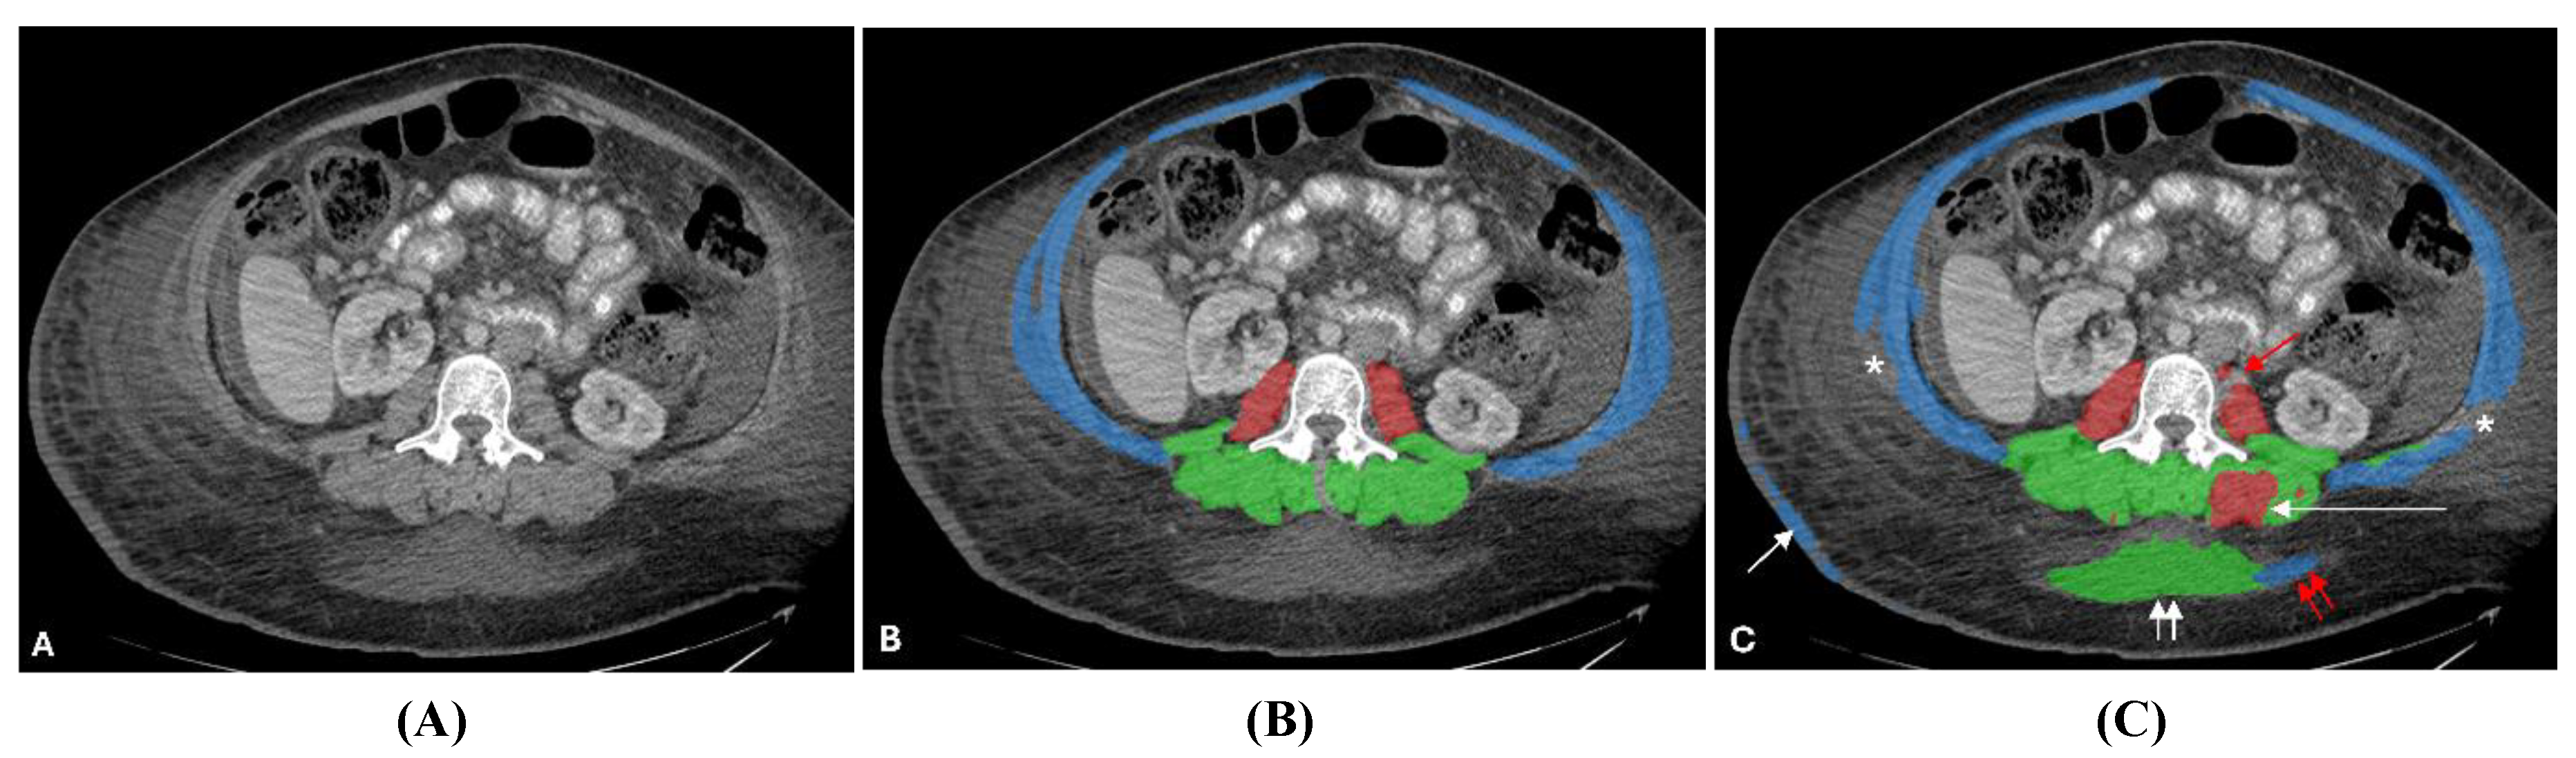

3.5. Qualitative Assessment and Error Analysis